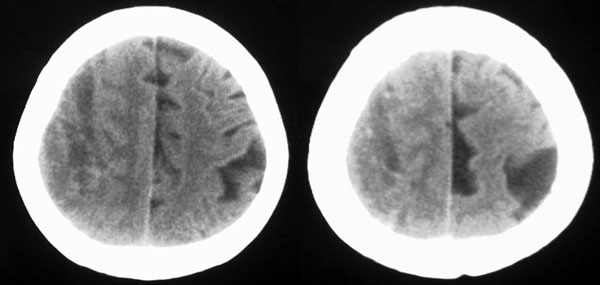

女87左下肢麻木,无外伤史

右颞顶部颅骨内板下新月形混杂密度影,右大脑皮层受压内移,考虑慢性硬膜下血肿,建议增强一下看看病灶,因为平扫好像显示的不是很好;左顶部软化灶

右侧大脑半球脑沟 脑裂变浅或消失,顶叶不规则低密度影,右侧侧脑室明显受压移位,中线偏移,右侧内板下新月形混杂高密度致密影,多考虑:慢性硬膜下血肿.必要时建议强化扫描.

右颞顶部颅骨内板下新月形混杂密度影,右大脑皮层受压内移,考虑慢性硬膜下血肿.

右额颞顶部颅骨内板下方新月形混杂密度影,同侧灰白界限受压内移,右侧脑室呈受压性改变,中线结构左移;左顶叶扫及片状脑脊样低密度区,另可见部分脑沟增宽

ct印象:1.右额颞顶部慢性硬膜下血肿

2.左顶叶软化灶

3.脑部分萎缩

右额颞顶部颅骨内板下方新月形混杂密度影,同侧灰白界限受压内移,右侧脑室呈受压性改变,中线结构左移;应该是右额颞顶部慢性硬膜下血肿,建议mri检查。

左顶叶片状低密度影,应是局限扩大的蛛网膜下腔。

右侧脑室前角受压变小,中线左移,考虑慢性硬膜下血肿.左侧脑软化灶.

右侧颞顶颅内板下可见新月状高低混杂密度影,右侧脑沟回消失,脑组织受压中线结构左移,考虑为右侧慢性硬膜下血肿。病人情况允许可做mri检查。我们遇到过几例没外伤史的病人有硬膜下出血的,多为六七十岁的老年患者,不知慢性硬膜下血肿与年龄有关否?